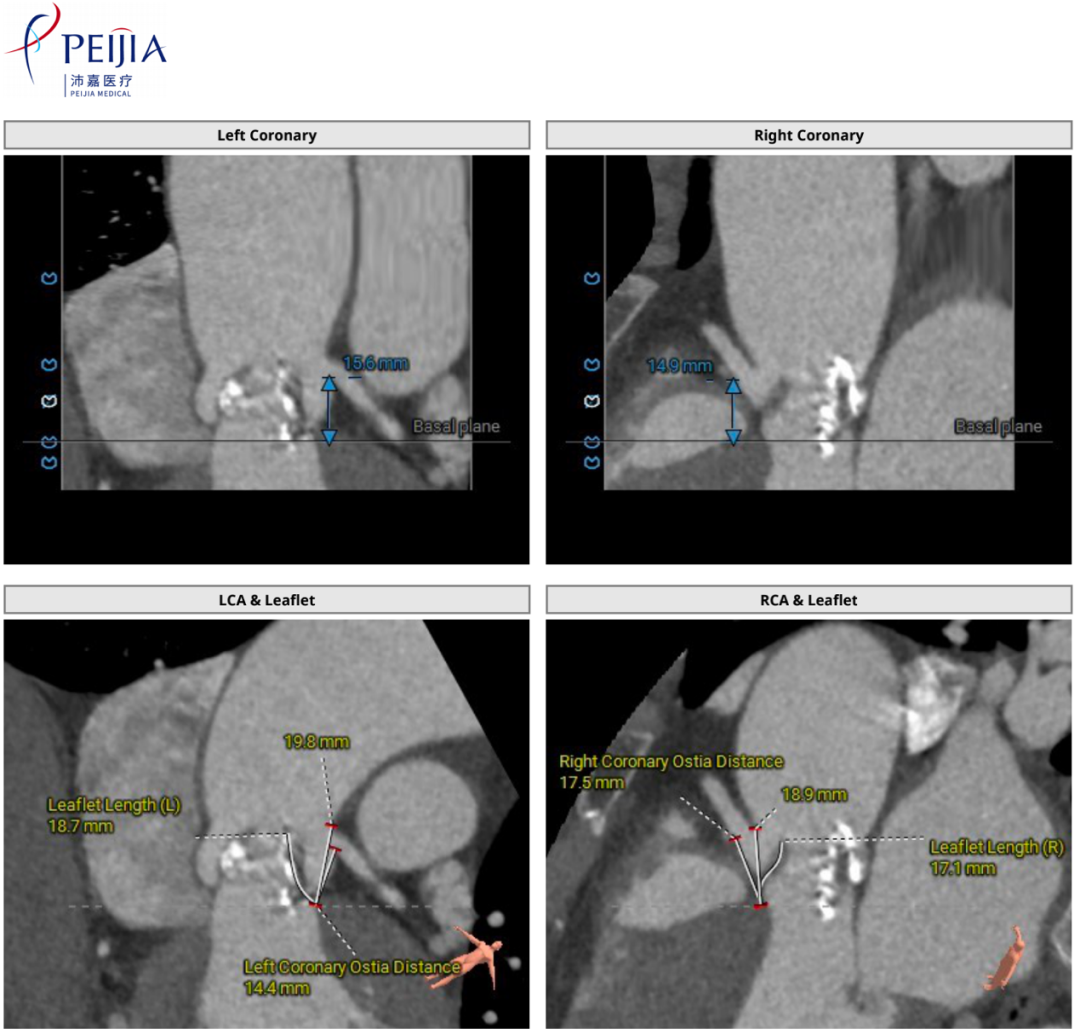

术前CT评估

2.冠脉开口高度尚可,左冠瓣叶稍冗长,切线位左冠瓣叶长度稍大于冠脉开口到瓣叶根部附着缘距离 ;

主动脉根部测量

瓣上结构测量

2.冠脉开口高度尚可,左冠瓣叶稍冗长,切线位左冠瓣叶长度稍大于冠脉开口到瓣叶根部附着缘距离,综合分析冠脉堵塞风险尚可,术中密切关注冠脉血流灌注;

随着TAVR技术在国内的普及,主动脉瓣狭窄患者有了更多的治疗选择。本例患者为主动脉瓣重度狭窄伴轻度反流,患者伴代偿性心力衰竭,术前评估适宜行TAVR手术,有TAVR手术指征。术前CT分析提示患者为Type0型二叶式主动脉瓣,瓣环径23.5mm,瓣叶增厚伴重度钙化,钙化主要分布于无窦与左窦交合缘及瓣叶边缘,LVOT呈类直筒状形态,预估人工瓣膜会有较明显形变,有根部撕裂、损伤风险。左室流出道可提供辅助锚定,综合预估瓣膜锚定定位精度要求较高。患者又为横位心,主动脉弓距及夹角尚可,升主动脉扩张,需警惕血管夹层、破裂等风险,对经导管主动脉瓣输送系统过弓、跨瓣的性能要求较高。综合以上因素,该患者行TAVR手术对术者快速、精准的操作能力及手术团队的密切配合要求较高。广东省人民医院赣州医院(赣州市立医院)倪忠涵院长带领团队,经过心内科、心外科、麻醉科、超声等多学科团队的缜密讨论,最终决定为患者施行TAVR手术治疗。